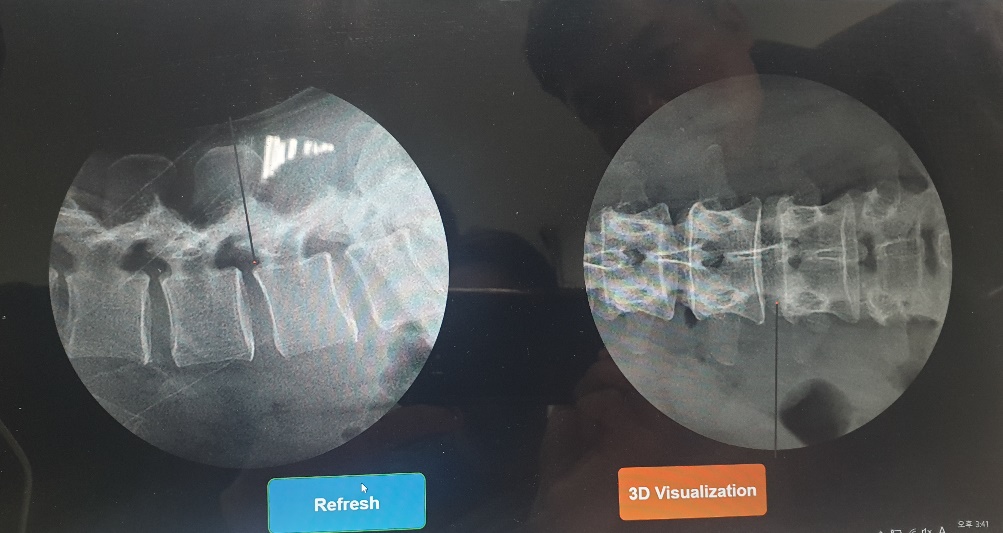

• Real-time image processing using 2 channel high-speed and high-resolution cameras.

Simulator based on Image Processing